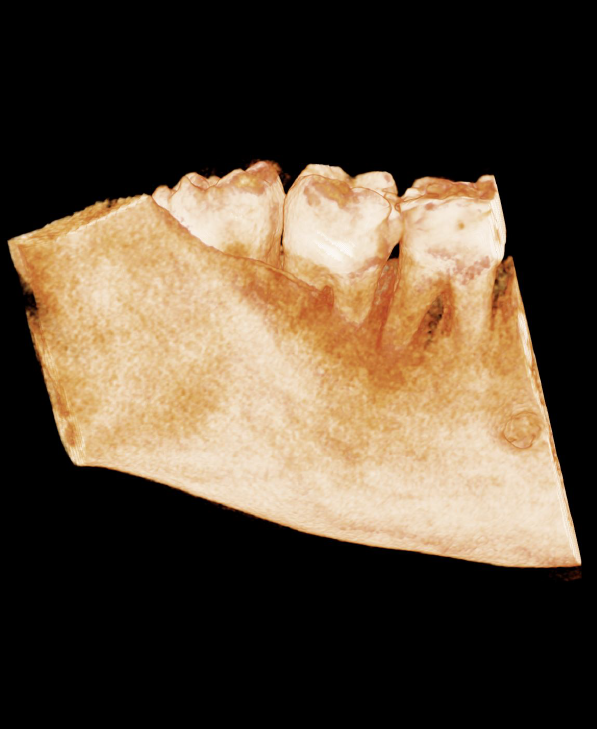

The LR8 is impacted, the apices are not close to the mandibular canal. There is an enlarged follicle space which does not have the typical appearance of an odontogenic cyst and is likely to be from past episodes of pericoronitis.